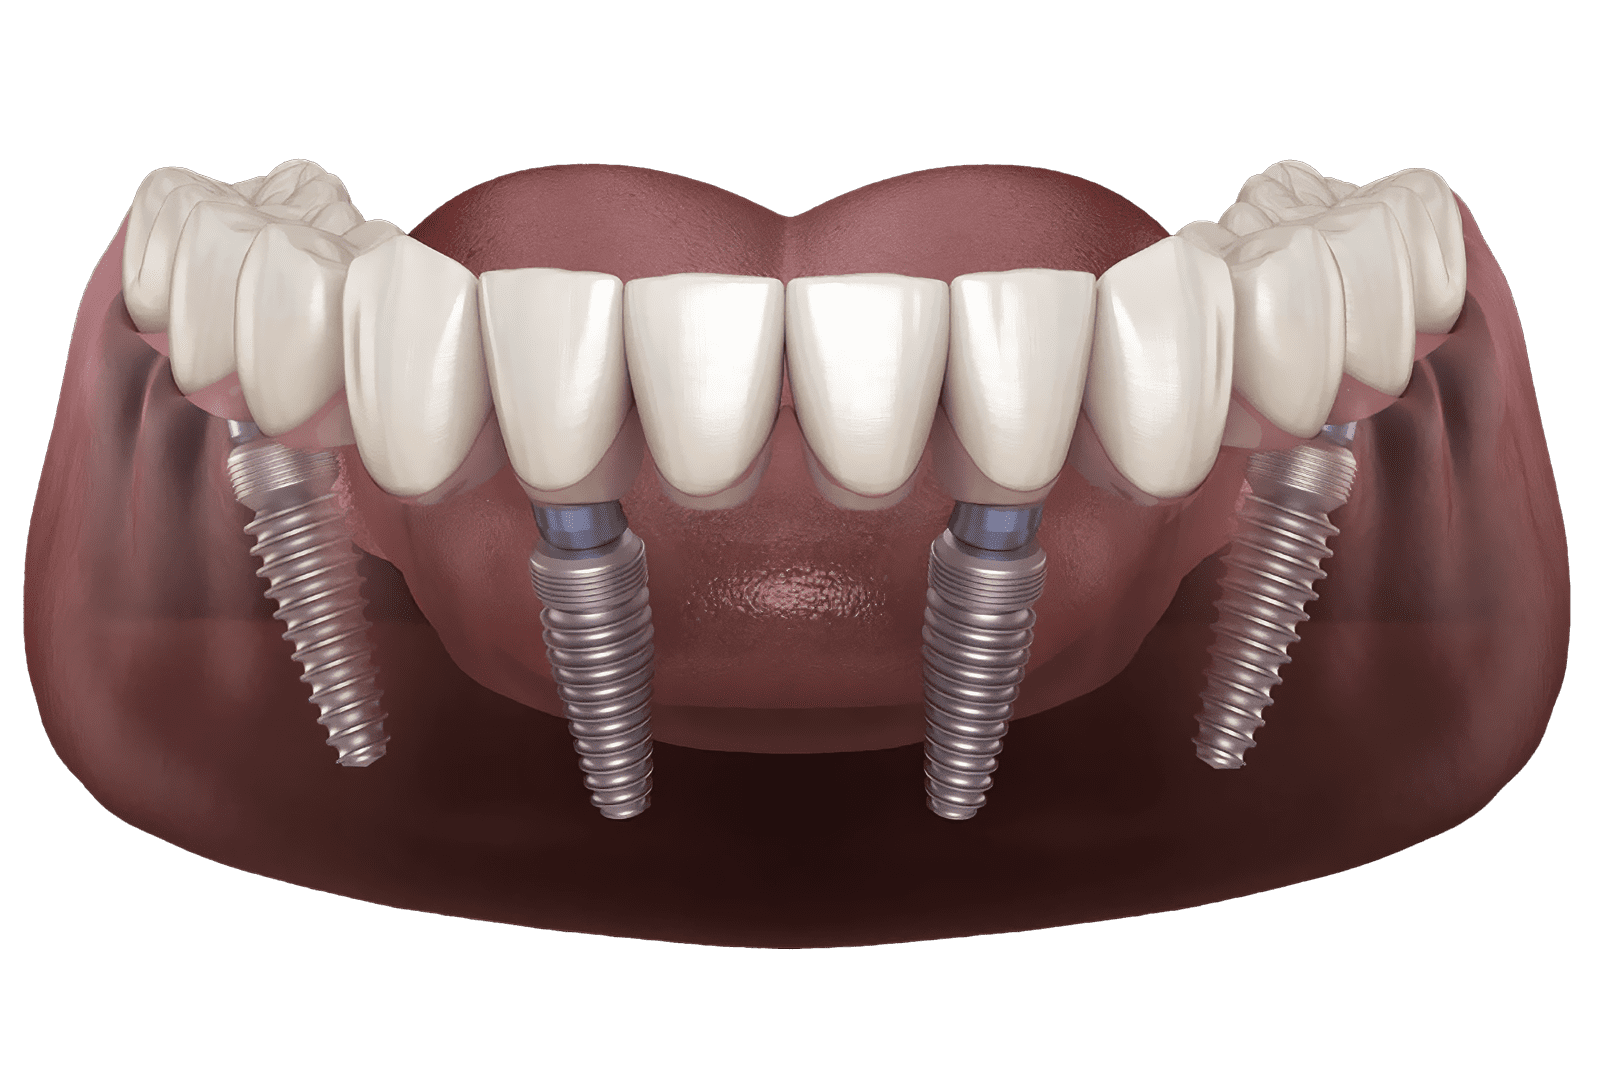

All on Four, üst ya da alt diş setinin yalnızca dört implantla değiştirildiği bir implant tekniğidir. Bu dört implant yeni bir diş setinin yerleştirilmesi için bir destek mekanizması görevini üstlenir.

All On Four dental implant prosedürüyle posterior implantlar ağzın arkasına doğru 45 derece yatırılarak çenenin daha yüksek kemik yoğunluğuna sahip bir bölgesi olan ön maksillaya yerleştirilir. Ağzın önüne yerleştirilmiş iki implant ve arkaya yerleştirilmiş iki açılı implant ile tam ark için destek sağlanması için yalnızca dört implanta ihtiyaç duyulur. Bu dört implant 10-14 dişe sahip sabit bir protezi destekleyebilir.

Diş kaybı genellikle çene kemiği kaybını da beraberinde getirir. Buna bağlı olarak çene kemiğinin yeniden yapılandırılması için kemik greftini gerektirir. All On Four tekniğinde implantların arka bölgelere açılı bir şekilde yerleştirilmesi kemik grefti ihtiyacını ve bunun için zaman harcanması gerekliliğini ortadan kaldırır.

All On Four tekniğinde ilk olarak ölçü alınarak hastaların geçici protezleri hazırlanır. Çekilecek dişlerin olması durumunda bunlar çekilir ve implantlar yerleştirilir. İmplantların üzerinden olacak şekilde hastalardan ölçü alınarak yapılan geçici protezler implantlara uygulanır.